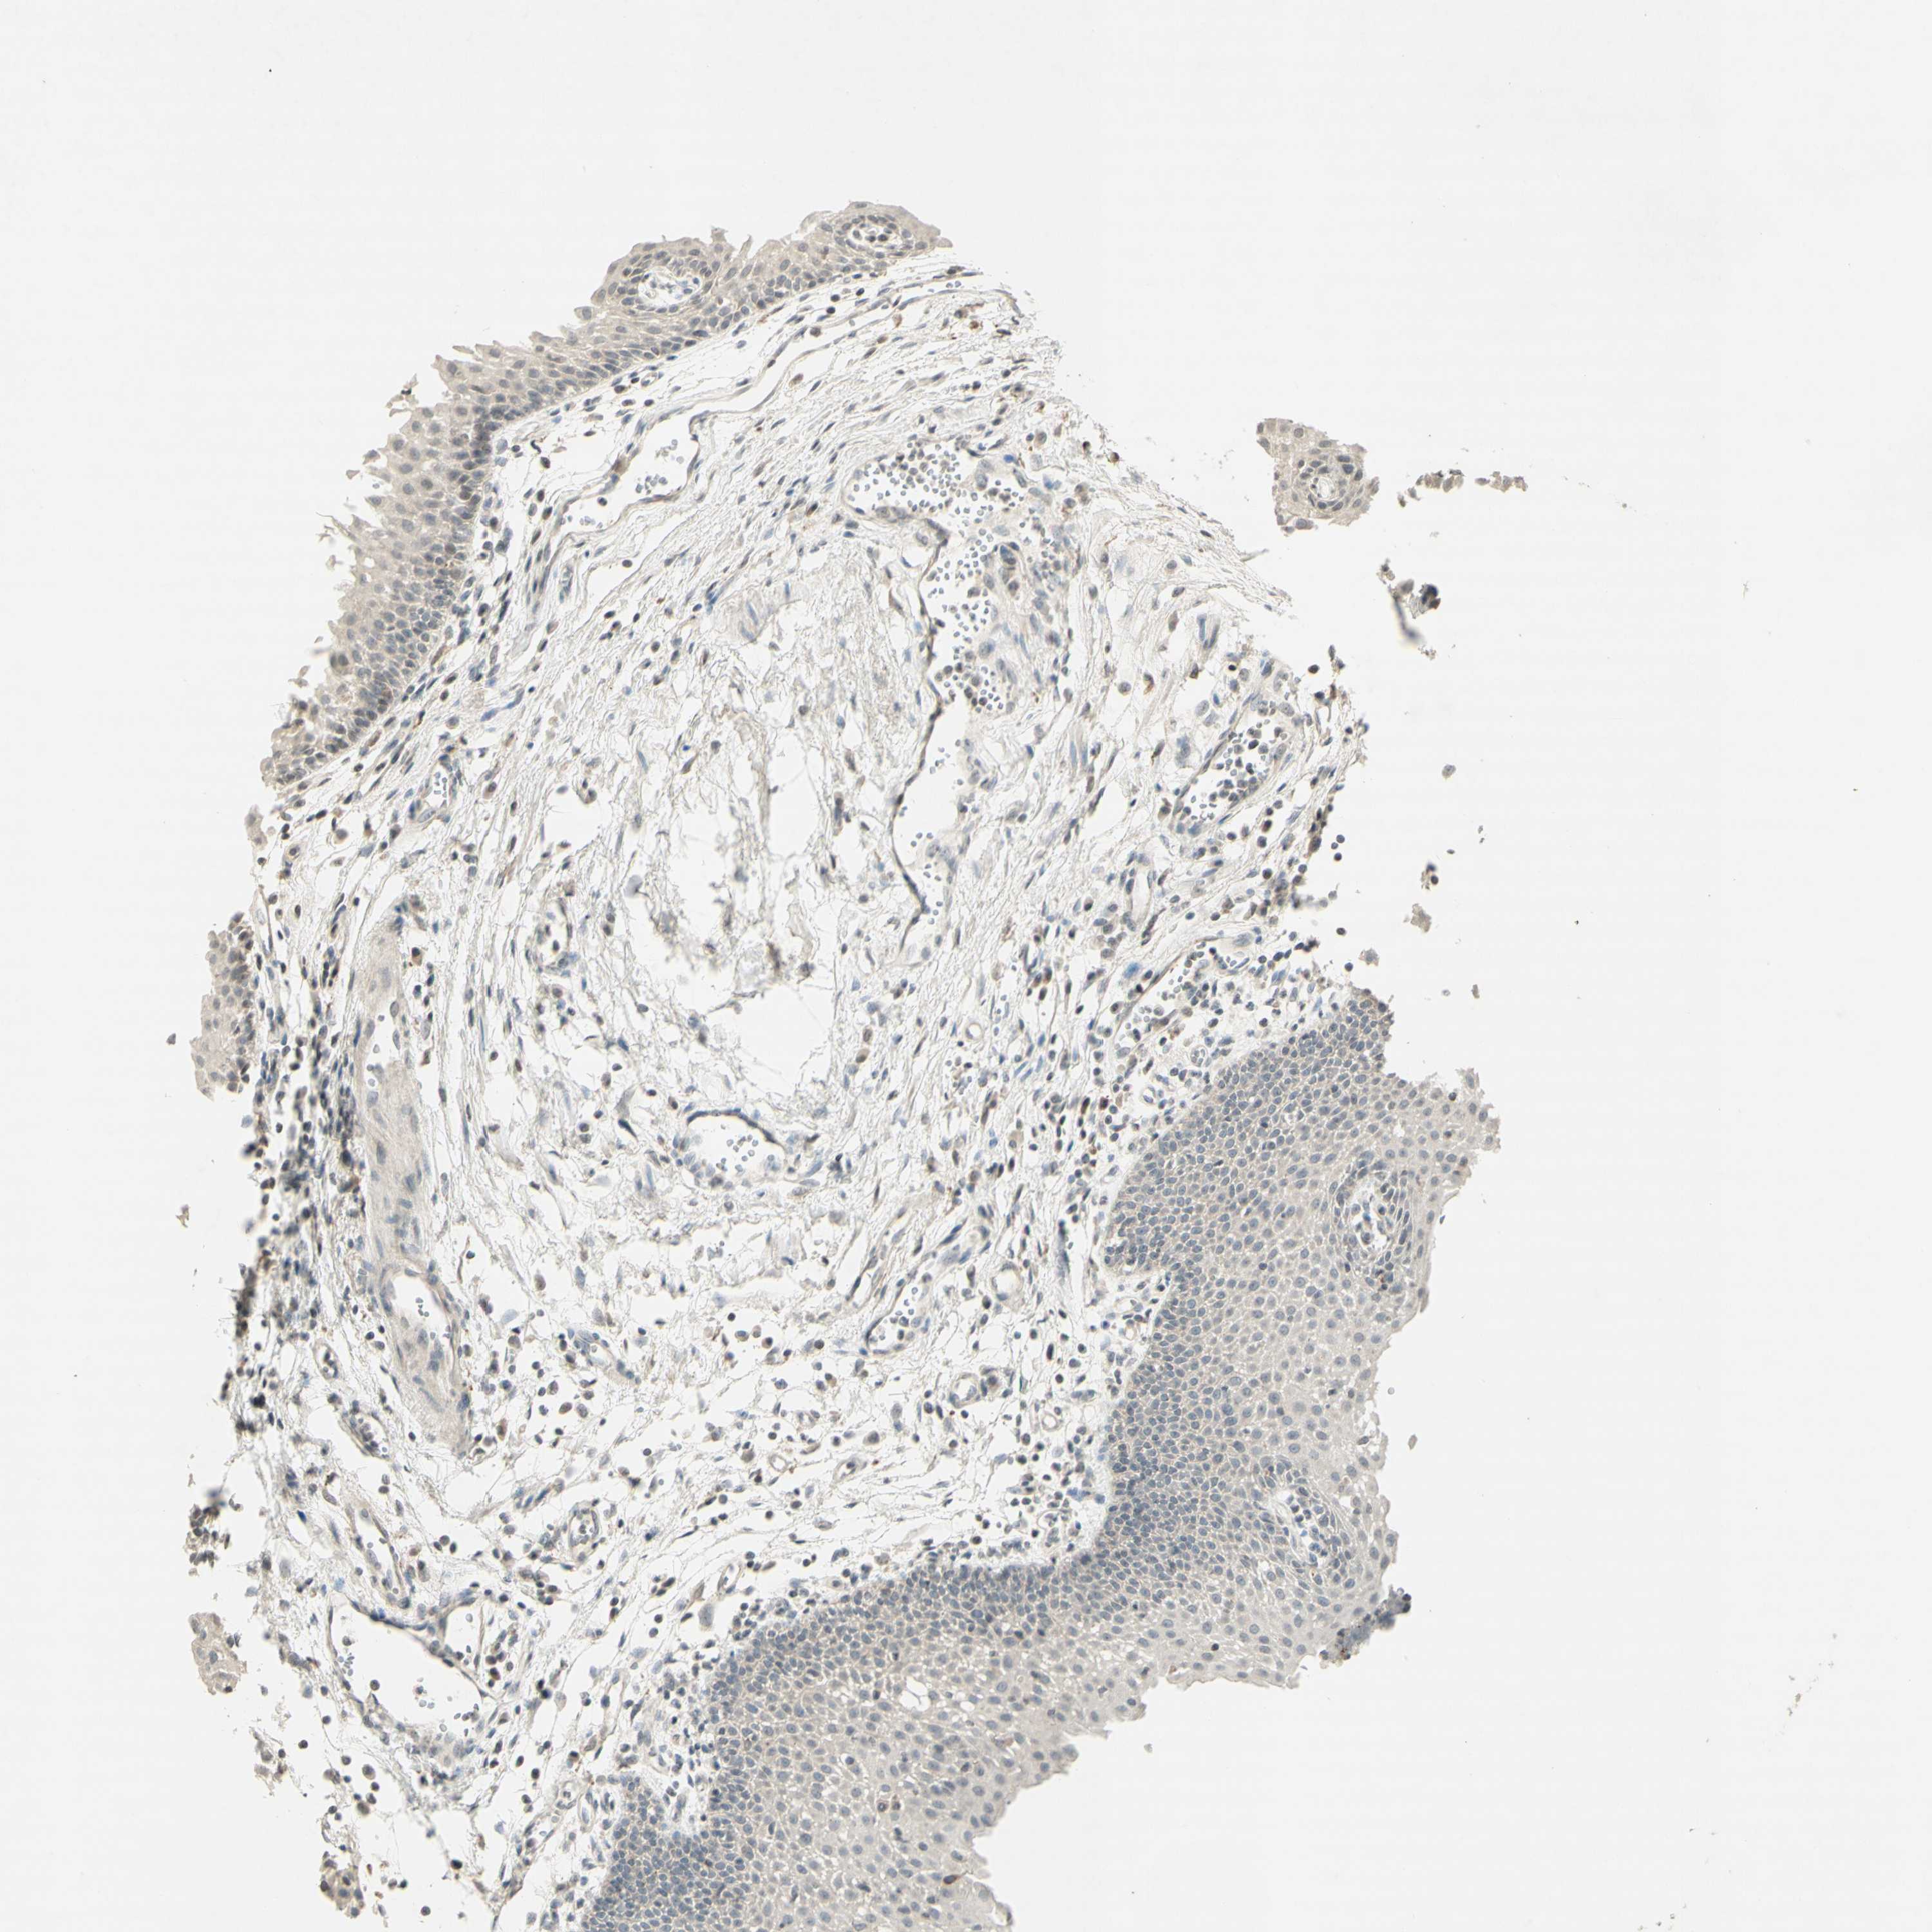

UROTHELIAL CANCER - Protein expressioni

A mouse-over function shows sample information and annotation data. Click on an image to view it in a full screen mode. Samples can be filtered based on level of antibody staining by selecting one or several of the following categories: high, medium, low and not detected. The assay and annotation is described here.

Note that samples used for immunohistochemistry by the Human Protein Atlas do not correspond to samples in the TCGA dataset.

Antibody stainingi

Antibody staining in the annotated cell types in the current human tissue is reported as not detected, low, medium, or high, based on conventional immunohistochemistry profiling in selected tissues. This score is based on the combination of the staining intensity and fraction of stained cells.

Each image is clickable and will lead to virtual microscopy that enables deeper exploration of all samples and also displays staining intensity scores, fraction scores and subcellular localization as well as patient and tissue information for each sample.

Antibody CAB009460

Staining

High

Medium

Low

Not detected

Intensity

Strong

Moderate

Weak

Negative

Quantity

>75%

75%-25%

<25%

None

Location

Nuclear

Cytoplasmic/membranous

Cytoplasmic/membranous,nuclear

Urothelial carcinoma, Low grade